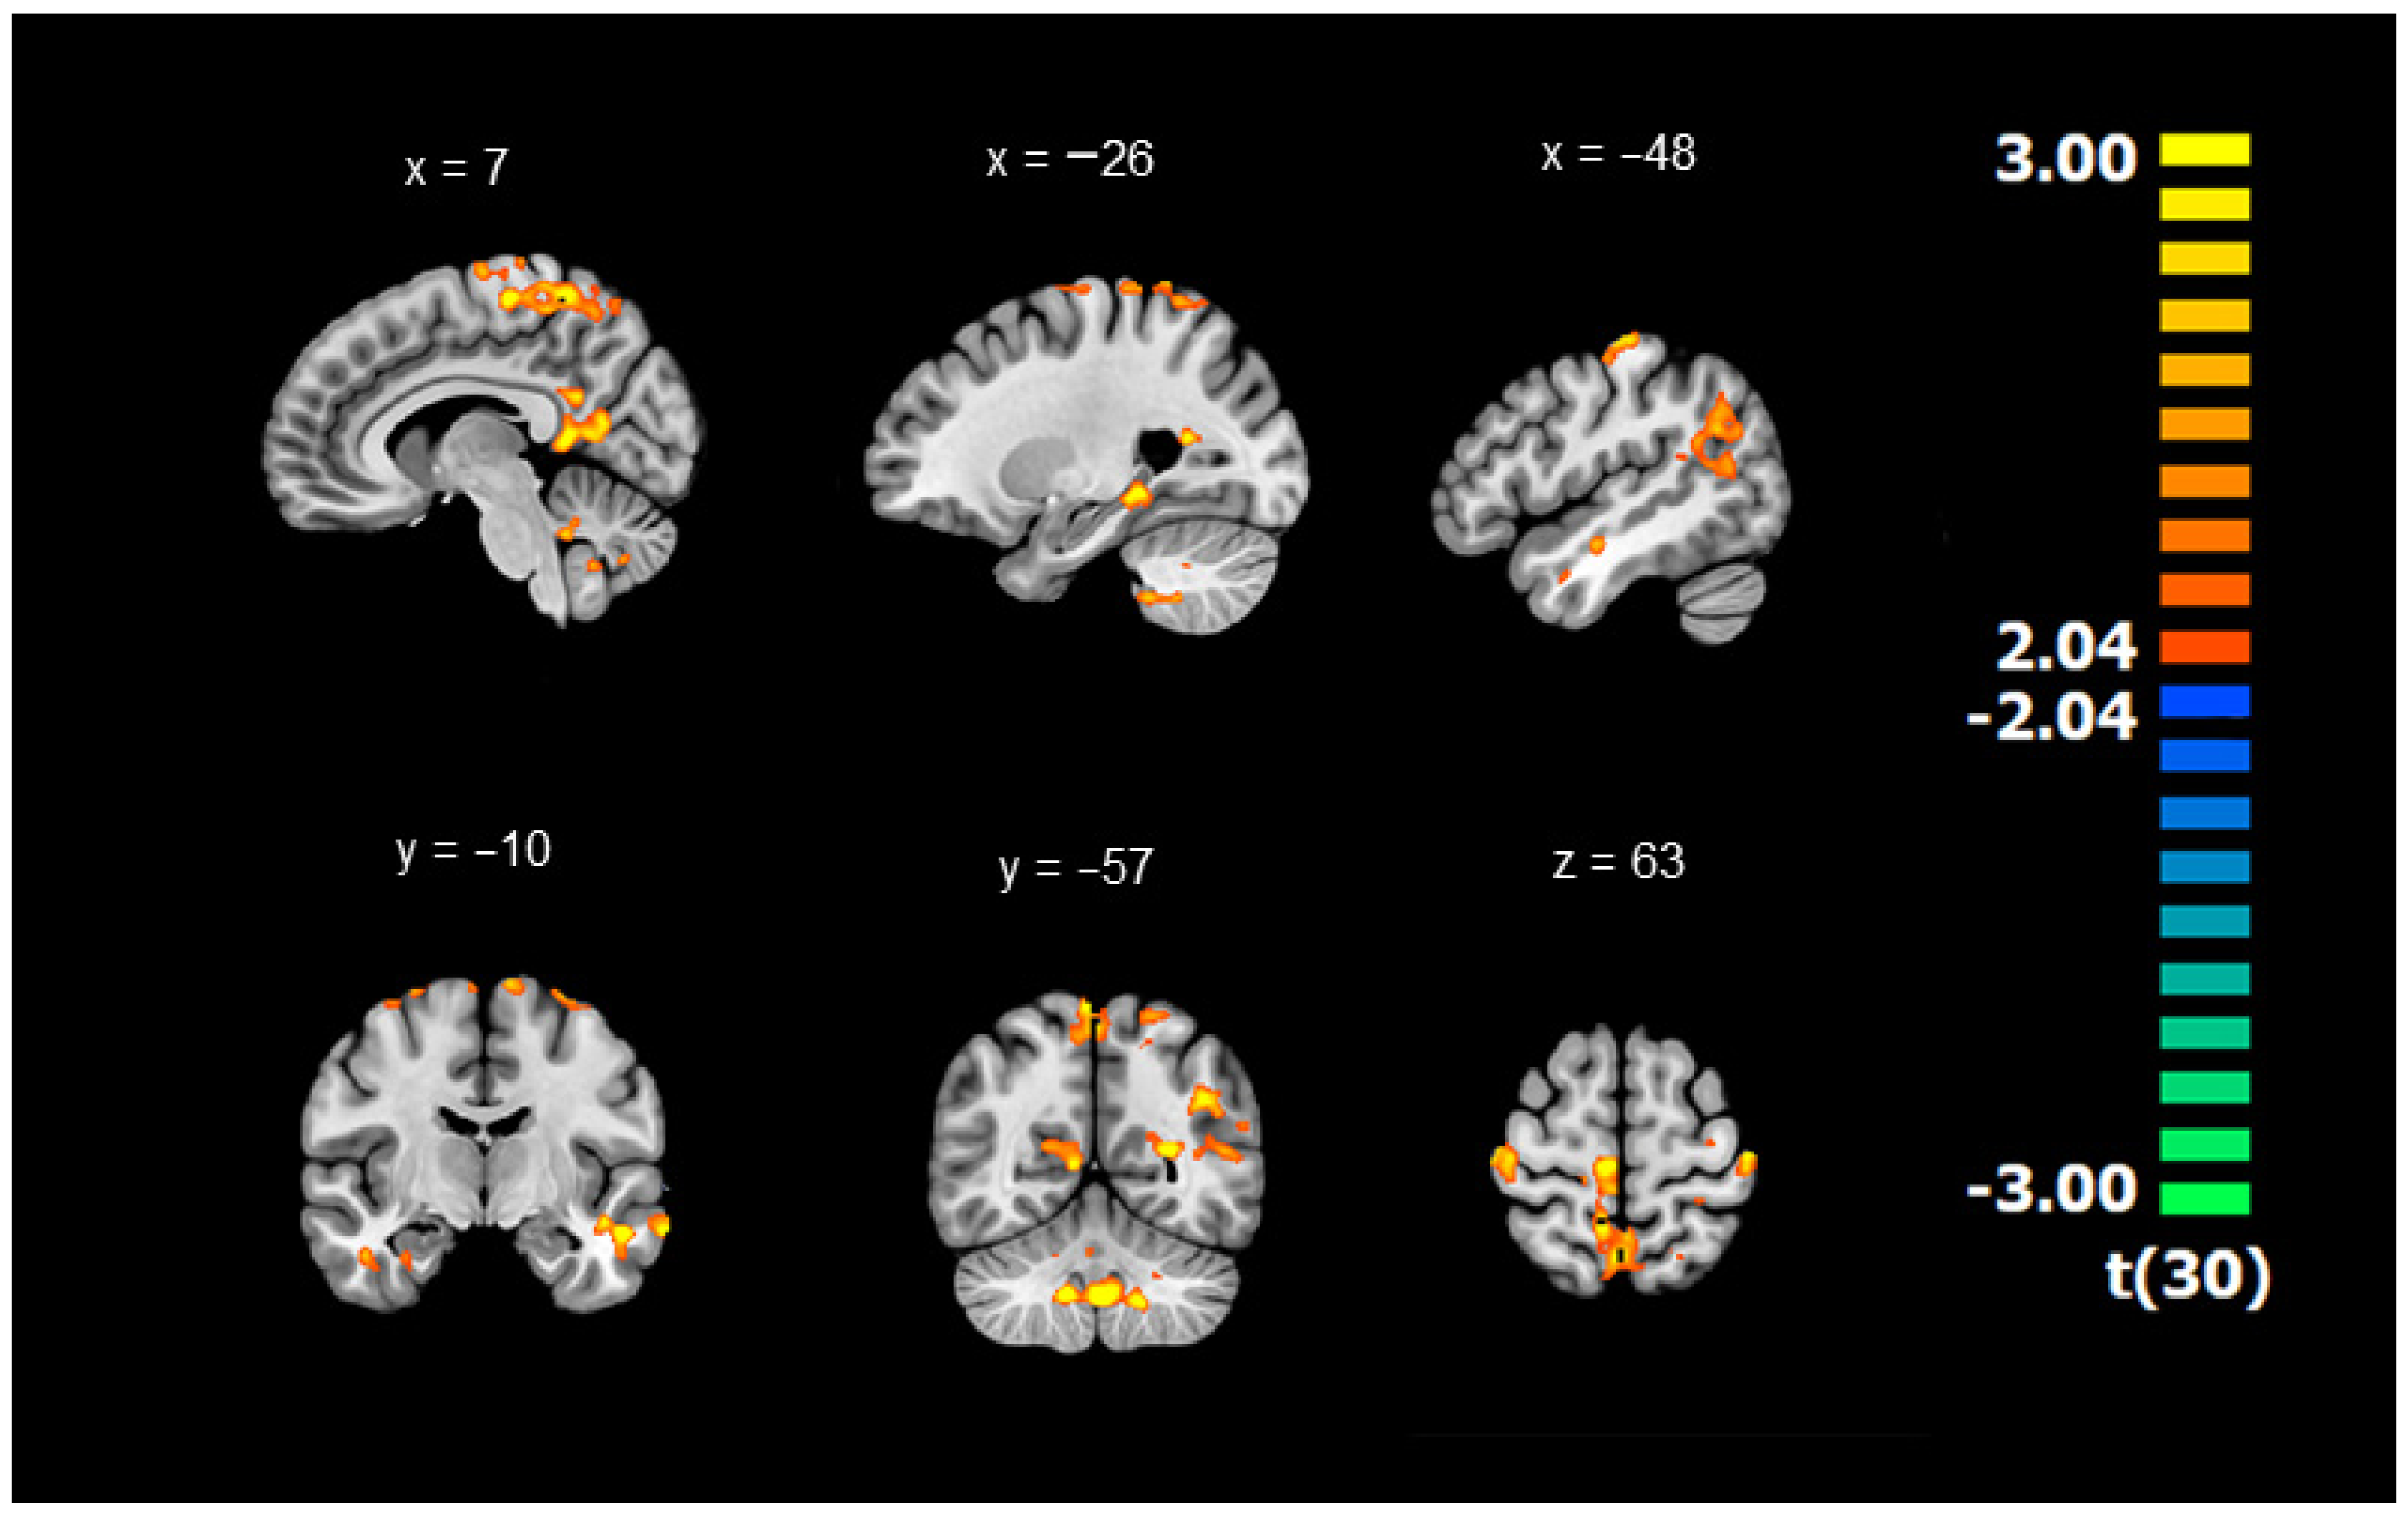

3.1. Differences in Connectivity between DYS and TD Children (Whole-Brain ANOVAs with the GMFA Seed Region)

| Correlated Brain Area (DYS < TD) | MNI Peak | |||||||

|---|---|---|---|---|---|---|---|---|

| Size | x | y | z | t(30) | ||||

| 13,639 | Cluster 1 | Bilateral Frontoparietal | −11 | −36 | 68 | 2.43 | ||

| L | Paracentral Lobule | BA 6 | −4 | −25 | 69 | 3.04 | ||

| L | Postcentral Gyrus | BA 2 | −49 | −22 | 63 | 2.88 | ||

| L | Postcentral Gyrus | BA 5 | −18 | −35 | 76 | 3.04 | ||

| L | Postcentral Gyrus | BA 5 | −33 | −35 | 71 | 3.09 | ||

| L | Precentral Gyrus | BA 4 | −36 | −22 | 69 | 2.81 | ||

| L | Precentral Gyrus | BA 4 | −37 | −16 | 67 | 2.80 | ||

| L | Precuneus | BA 7 | 2 | −57 | 67 | 2.99 | ||

| L | Superior Frontal Gyrus | BA 6 | −21 | −3 | 76 | 2.82 | ||

| R | Medial Frontal Gyrus | BA 6 | 5 | −13 | 74 | 2.80 | ||

| R | Paracentral Lobule | BA 5 | 8 | −39 | 59 | 2.83 | ||

| R | Paracentral Lobule | BA 6 | 6 | −24 | 64 | 3.05 | ||

| R | Postcentral Gyrus | BA 7 | 25 | −49 | 74 | 3.11 | ||

| R | Precuneus | BA 7 | 8 | −47 | 65 | 3.07 | ||

| 2943 | Cluster 2 | Right Frontoparietal | 40 | −21 | 65 | 2.38 | ||

| R | Postcentral Gyrus | BA 3 | 43 | −25 | 65 | 2.85 | ||

| R | Postcentral Gyrus | BA 3 | 34 | −26 | 72 | 2.88 | ||

| R | Precentral Gyrus | BA 4 | 32 | −16 | 72 | 2.84 | ||

| 4263 | Cluster 3 | Bilateral Limbic | 6 | −52 | 13 | 2.49 | ||

| L | Posterior Cingulate | BA 29 | 0 | −46 | 7 | 3.09 | ||

| R | Posterior Cingulate | BA 30 | 19 | −62 | 14 | 2.95 | ||

| R | Posterior Cingulate | BA 30 | 7 | −60 | 12 | 2.90 | ||

| R | Posterior Cingulate | BA 30 | 6 | −51 | 24 | 2.85 | ||

| 1693 | Cluster 4 | Right Limbic | BA 34 | 37 | −3 | −28 | 2.32 | |

| R | Parahippocampal Gyrus | BA 34 | 33 | 1 | −28 | 2.85 | ||

| R | Parahippocampal Gyrus | Amygdala | 33 | −4 | −22 | 2.91 | ||

| 5940 | Cluster 5 | Left Temporolimbic | −39 | −56 | 23 | 2.39 | ||

| L | Posterior Cingulate | BA 31 | −15 | −50 | 23 | 3.05 | ||

| L | Superior Temporal Gyrus | BA 39 | −43 | −56 | 33 | 2.91 | ||

| 1766 | Cluster 6 | Left Temporolimbic | −31 | −35 | −15 | 2.44 | ||

| L | Parahippocampal Gyrus | Hippocampus | −28 | −37 | −8 | 3.12 | ||

| L | Parahippocampal Gyrus | BA 35 | −32 | −31 | −24 | 2.86 | ||

| L | Fusiform Gyrus | BA 20 | −35 | −38 | −17 | 2.83 | ||

| 3621 | Cluster 7 | Left Temporal | −58 | −9 | −18 | 2.48 | ||

| L | Superior Temporal Gyrus | BA 38 | −40 | 20 | −36 | 2.92 | ||

| L | Fusiform Gyrus | BA 20 | −40 | −5 | −27 | 3.34 | ||

| L | Sub-Gyral | BA 21 | −46 | −11 | −16 | 2.91 | ||

| L | Middle Temporal Gyrus | BA 21 | −55 | −4 | −18 | 3.10 | ||

| L | Middle Temporal Gyrus | BA 21 | −65 | −3 | −18 | 2.82 | ||

| L | Middle Temporal Gyrus | BA 21 | −68 | −13 | −16 | 3.22 | ||

| 7273 | Cluster 8 | Bilateral Cerebellum | 4 | −52 | −41 | 2.52 | ||

| L | Posterior Lobe | Lob X | −22 | −41 | −46 | 2.43 | ||

| L | Posterior Lobe | Lob IX | −6 | −55 | −42 | 2.73 | ||

| R | Posterior Lobe | Lob IX | 10 | −54 | −42 | 2.52 | ||

| R | Posterior Lobe | Dentate | 17 | −52 | −34 | 2.29 | ||

| R | Anterior lobe | Lob V | 17 | −51 | −27 | 2.20 | ||

| R | Posterior Lobe | Lob X | 24 | −39 | −44 | 2.51 | ||

| R | Posterior Lobe | Lob VIIIa | 32 | −45 | −47 | 2.50 | ||

| R | Anterior Lobe | Crus I | 44 | −42 | −37 | 2.46 | ||